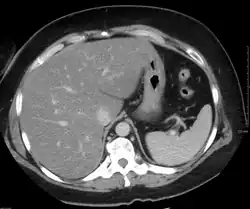

Imaging studies are often obtained during the evaluation process. Ultrasonography reveals a "bright" liver with increased echogenicity. Pocket-sized ultrasound devices might be used as point-of-care screening tools to diagnose liver steatosis.[30] Medical imaging can aid in diagnosis of fatty liver; fatty livers have lower density than spleens on computed tomography (CT), and fat appears bright in T1-weighted magnetic resonance images (MRIs). Magnetic resonance elastography, a variant of magnetic resonance imaging, is investigated as a non-invasive method to diagnose fibrosis progression.[31]